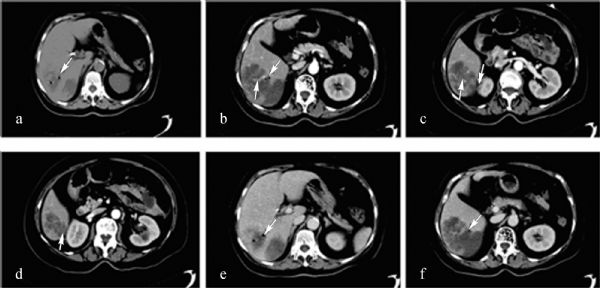

Nowadays, pyogenic liver abscess (PLA) is still a common and severe intra-abdominal infection, and Klebsiella pneumoniae had emerged as the most common pathogenic bacteria worldwide in the past ten years. Our study aims to achieve an early pathogenic diagnosis and rational therapy modality for Klebsiella pneumoniae liver abscess (KLA) through clinical data analysis. A total of 197 inpatients in Zhongshan Hospital, Shanghai, diagnosed as having liver abscess between March 2001 and September 2009 were enrolled. Patients with monomicrobial infection were divided into two groups: patients with K. pneumoniae liver abscess (KLA group, n=106) and those with non-Klebsiella pneumoniae liver abscess (NKLA group, n=56). A retrospective analysis was made between these two groups on the aspects of underlying diseases, clinical characteristics, laboratory data, culture results, and imaging findings. To evaluate the effects of different medical interventions, monomicrobial KLA patients were further divided into four subgroups (percutaneous liver aspiration, aspiration plus antibiotics flushing, aspiration plus retained catheter, and aspiration plus antibiotics flushing and retained catheter), and corresponding therapeutic effects were analyzed. KLA was more likely to occur in patients with coexisting diseases such as diabetes mellitus (53.77% vs 25.00%, P=0.001) and hepatic adipose infiltration (16.04% vs 5.36%, P=0.029). Compared to NKLA group, clinical characteristics including abdominal pain (40.57% vs 57.14%, P=0.044), hypodynamia (19.81% vs 46.43%, P=0.001), and hepatomegaly (4.72% vs 14.29%, P=0.033) were much milder, but with a higher fasting blood glucose level (7.84€±€0.36 vs 5.76€±€0.30, P=0.001) on admission in KLA group. In addition, KLA abscess often appeared singly in the right lobe of the liver with gas forming nature (32.88% vs 13.51%, P=0.039), unsmooth rim (71.23% vs 40.54%, P=0.002), and dynamic septum enhancement (41.10% vs 16.22%, P=0.009). Compared to mono aspiration subgroup, additional antibiotic flushing could not further improve clinical outcomes of KLA patients (P>0.05); however, the retained catheter showed obvious advantage in reducing abscess diameter (34.38€±€3.25 mm vs 22.67€±€2.37 mm, P=0.017). It can be concluded that the strong association with diabetes, milder clinical symptoms, and gas-forming nature in CT images makes early pathogenic diagnosis of KLA possible. Comparatively, ultrasonography-guided percutaneous liver aspiration with retained catheter may be the most rational intervention modality of KLA.